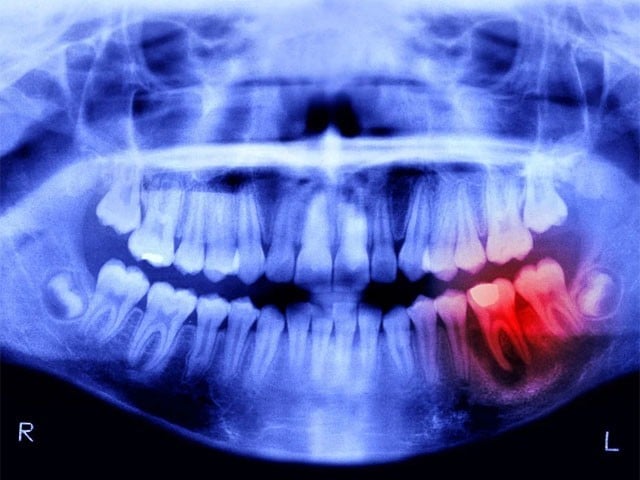

اوساکا: جاپانی سائنس دانوں نے ایک ایسی دوا تیار کی ہے جو انسانی دانت کو دوبارہ اُگا سکتی ہے۔جاپان کے شہر اوساکا میں قائم کٹانو ہاسپٹل اور کیوٹو یونیورسٹی سے تعلق رکھنے والے کاٹسو تاکا ہاشی کا کہنا تھا کہ سائنس دان ایسے افراد جن کے دانت گِر رہے ہوں یا گِر چکے ہوں کی مدد کے لیے کچھ کرنا چاہتے تھے۔ یہ پیشرفت یوٹیرین سینسیٹائزیشن-ایسوسی ایٹڈ جین-1 (یو ایس اے جی-1) نامی اینٹی باڈی کا سالوں تک معائنہ کرنے کے بعد سامنے آئی ہے، جس کو چوہوں اور فیریٹ کے دانت کی نمو میں رکاوٹ پیدا کرتے ہوئے دیکھا گیا تھا۔2021 میں کیوٹو سے تعلق رکھنے والے سائنس دانوں نے ایک مونو کونل اینٹی باڈی دریافت کی تھی جو یو ایس اے جی-1 کو بون مورفوجینیٹک پروٹین (بی ایم پی) نامی سالموں کے درمیان رابطے میں خلل ڈالتی تھی۔تحقیق کے شریک مصنف کاٹسو تاکا ہاشی کا جاری کی جانے والی پریس ریلیز میں کہنا تھا کہ سائنس دان یہ جانتے تھے کہ یو ایس اے جی-1 کو دبایا جانا دانت کی نمو کے لیے مفید ہوتا ہے۔ تاہم، یہ بات معلوم نہیں تھی کہ آیا ایسا کرنا کافی ہوگا یا نہیں۔ فیریٹس ڈائی فائیو ڈونٹ جانور ہوتے ہیں اور ان کی دانتوں کی ترتیب بالکل انسانوں کی طرح ہوتی ہے۔ سائنس دانوں کو اب یہ دیکھنا ہے کہ یہ مماثلت کس حد تک ہے کیوں کہ رواں برس ستمبر سے اس آزمائش کی ابتداء انسانوں پر کی جائے گی۔11 مہینوں تک جاری رہنے والی یہ تحقیق 30 سے 64 برس کے درمیان 30 مردوں پر کی جائے گی، جن کا کم از کم ایک دانت نہیں ہوگا۔واضح رہے جانوروں پر کی جانے والی تحقیق میں دوا کے کسی قسم کے مضر اثرات سامنے نہیں آئے ہیں۔